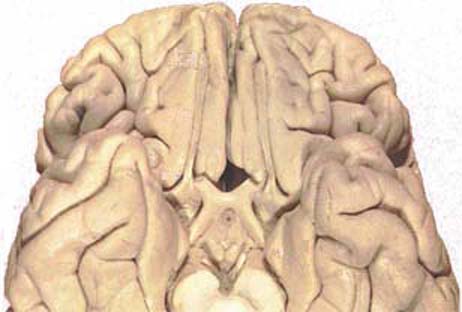

En écartant les berges de la fissure sagittale, on découvre le bec du corps calleux contre lequel chemine le segment antérieur du lobe intra-limbique fait de la bandelette diagonale (bd) et de l'indisium gris (ig).

Ce lobe comporte:

- le nerf olfactif proprement dit, fait d'une extrémité enflée, le bulbe (bo), et d'un cordon ou bandelette(bo); ce dernier aboutit à trois racines ou stries olfactives dont l'écartement encadre  l'espace perforé antéreiur.